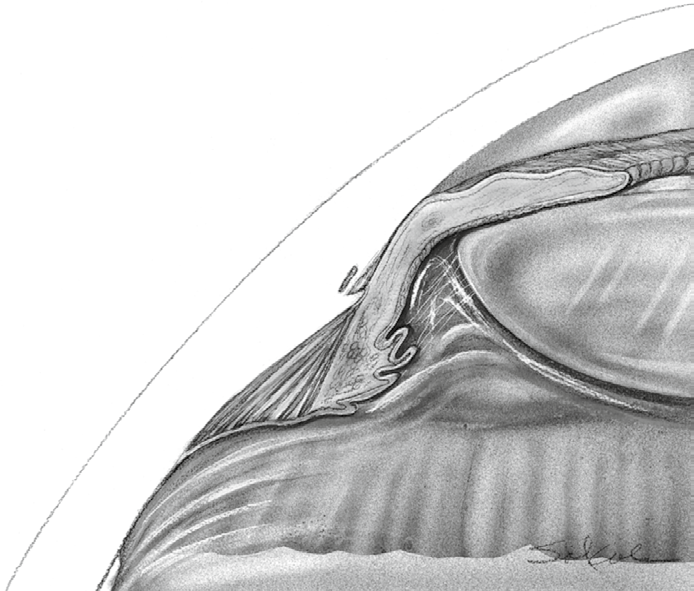

Question Image